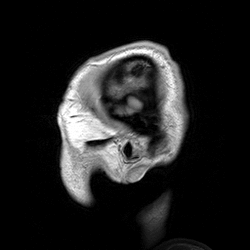

Итак начнем с названия, как расшифровывается МРТ? Магнитно-Резонансная Томография, и, в принципе, ответ на вопрос “как это работает?” дан уже в названии самой методики. На английском, кстати, МРТ - это MRI (Magnetic resonance imaging) и, как ни странно, на русском название несет в себе чуть больше смысла, так как используется термин томография, который пошел от древнегреческого слова τομή (сечение) и означает - послойное изображение внутренней структуры объекта. Все мы знаем, как выглядят классические снимки с МРТ - это именно слоистое изображение.